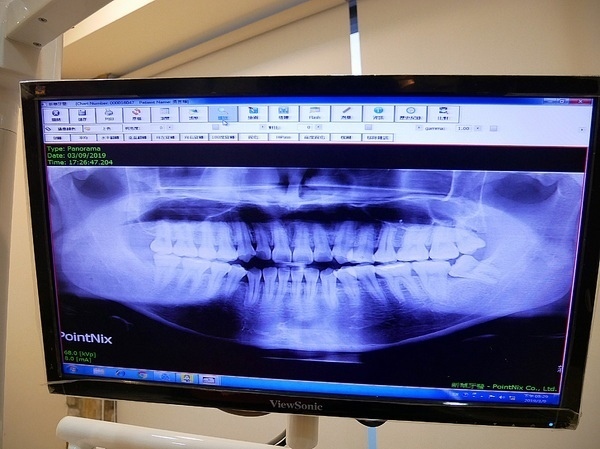

來獻醜啦!! 這就是我牙齒的X光片

最右邊就是我超煩惱的智齒

上下兩顆都長得歪七扭八 既不舒服又容易卡食物

這樣超容易造成蛀牙 而且還可能推擠到前面的牙齒

但聽到要鋸開才能拔 我就超級掙扎